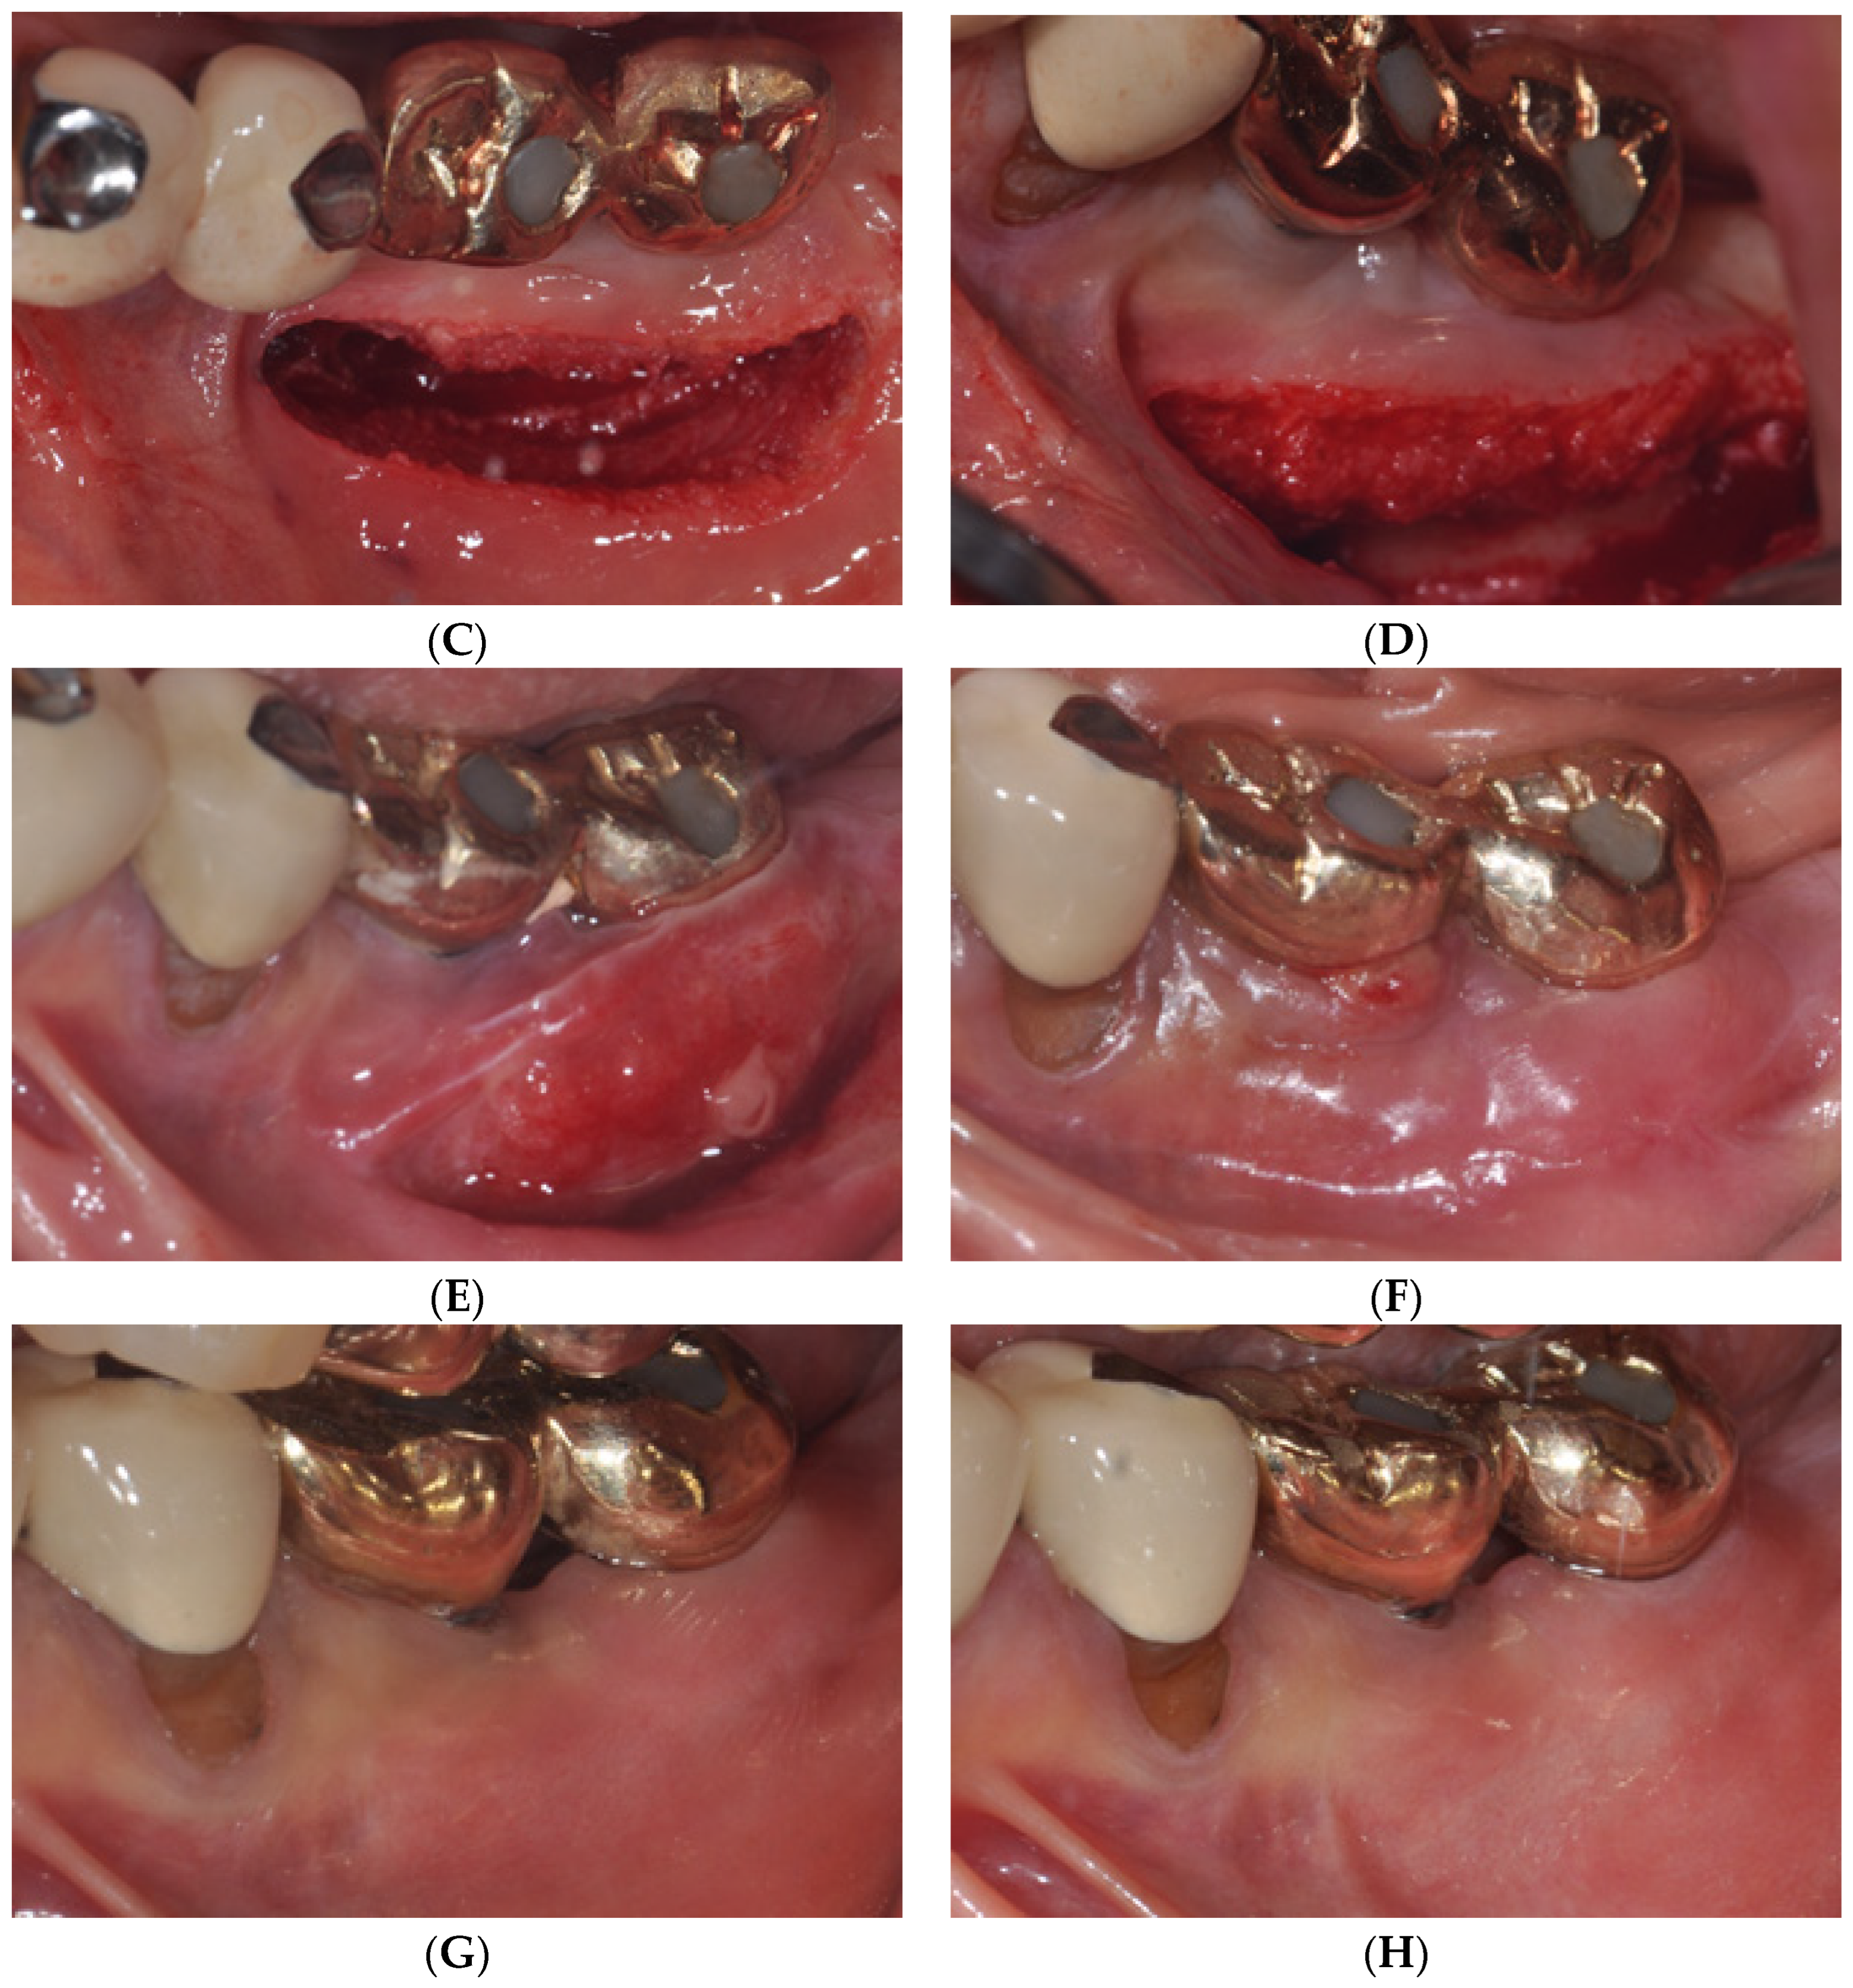

2.1. Surgical Procedures of Er:YAG Laser-Assisted Periosteal Fenestration (LA-PF)

2.2. Case